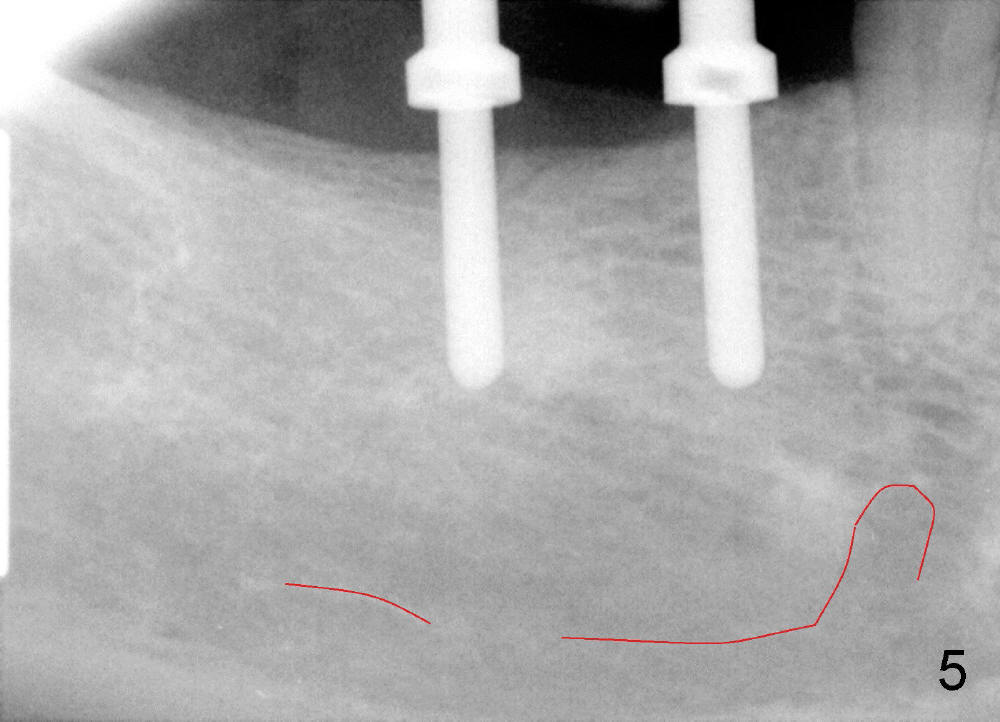

PA is taken after insertion of parallel pins at the depth of 10 and 8 mm at the sites of #30 and 31, respectively (Fig. 5, red line outlines the upper border of the inferior alveolar canal). It appears to be safe to increase the lengths of the implants by 2 mm.